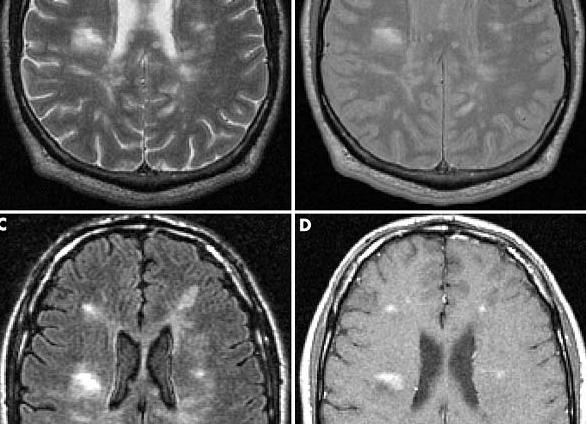

С помощью магнитно-резонансной томографии выявляют нарушения в мягких тканях. Рентген-аппарат определяет травмы и опасные внутренние кровотечения. Первое устройство отличается от второго возможностью представления изображения в трехмерном виде. Чтобы получить изображение в разных плоскостях с помощью рентгена, потребуется многократное рентгеновское облучение. В основе рентгена находятся электромагнитные высокочастотные волны. Они эффективны для диагностики пневмонии, отека и рака легких. Томография работает за счет магнитного поля, с помощью которого специалисты отличают нормальную ткань от патологической. Разница между рассматриваемыми устройствами заключается в том, что МРТ не применяет ионизирующее излучение. Подробнее ...